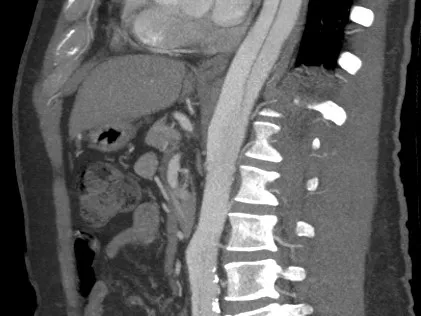

This module is created to provide guidance for radiologists who would like to gain confidence in identifying acute emergencies of the aorta and improve their reporting skills on the basis of a structured approach. Acute aortic syndrome belongs to the most fatal emergencies in the medical field and requires immediate diagnosis on CT scan which is the quickest and most reliable tool for assessment of the aortic pathology and urgent differential diagnosis. The radiologist’s role is not only to detect or rule out the acute pathology, but also to provide the clinicians with the most important details and identify risk factors and associated complications which have an impact on the immediate and targeted further management of the high-risk patients.

The training contains 5 anonymised real-life cases from everyday reporting in the TMC on-call section.